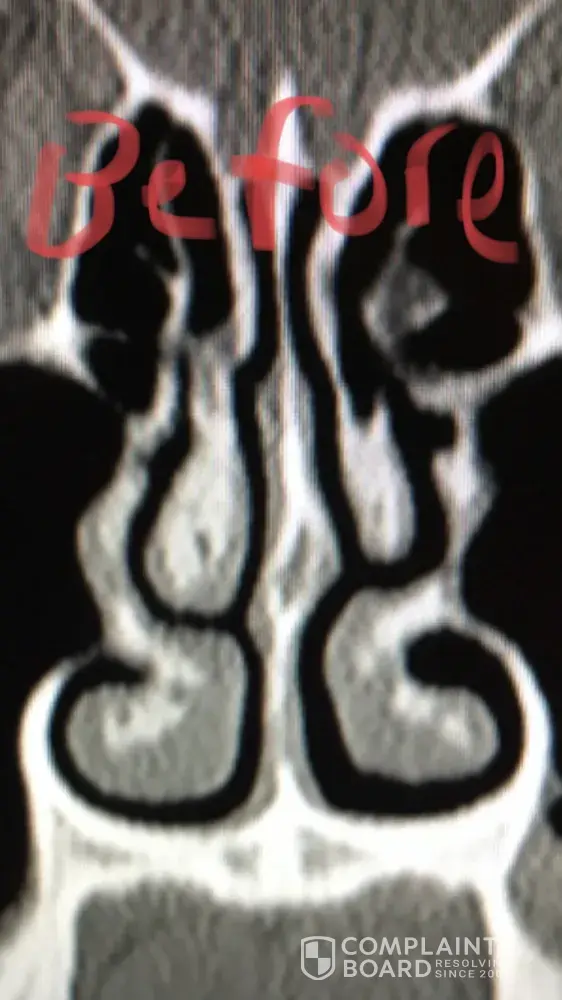

For people reading this, I have included x-ray images of the inside of my nose, before and after my surgery with him. As you can see from these images, my nasal airway was equally open on both sides, before surgery, and the septoplasty didn't need to be done. By performing it, he severely narrowed the right side of my nasal airway.

He performed this unnecessary surgery to collect that additional insurance money. There is no other explanation for this. Furthermore, when I later contacted him, and told him that my breathing was worse, and I suspected it was a problem with my septum, he told me that he wouldn't be able to perform the revision septoplasty (make the septum way it was before). Therefore, not only is he greedy, by performing unnecessary surgeries, but he is incompetent, for not being able to fix his mistakes.

Dr Raviv performed two surgeries on me: endoscopic sinus surgery (where they widen the sinus passages), and septoplasty (where they straighten the septum). The septoplasty, however was completely unnecessary, and severely narrowed the right side of my nasal airway. For people reading this, I have included x-ray images of my sinuses, before and after my surgery with Dr. Raviv. As you can see from the surgery, my airway was much more open, and equal on both sides, before my surgery with him.